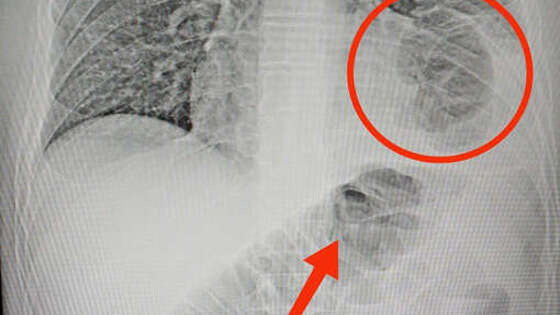

Хирурги Нижнекамской центральной районной больницы оказали помощь пациенту с нетипичным расположением грыжи. Об этом сообщает Минздрав республики. 46-летний мужчина обратился в медицинское учреждение с жалобами на боли в животе. В ходе обследования медики обнаружили, что в грудной клетке пациента находится часть кишечника. Оказалось, у мужчины была ущемленная грыжа диафрагмы – редкое состояние, при котором органы брюшной полости через отверстие в диафрагме попадают в грудную клетку. Причиной патологии могло стать ножевое ранение, полученное нижнекамцем восемь лет назад. Было принято решение о проведении хирургического вмешательства. "Врачи аккуратно извлекли ущемленную кишку из грудной клетки, проверили, нет ли омертвевших участков. После устранили дефект диафрагмы, зашив отверстие", - сообщили в Минздраве. Операция длилась два часа и прошла успешно, пациент уже идет на поправку.